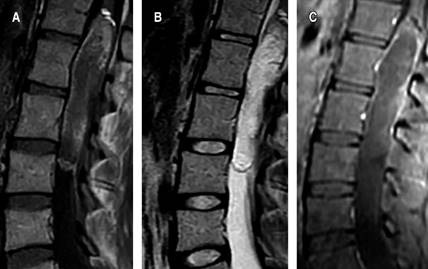

Female patient, 26 years old, with a history of pain in the right pelvic member of six years of evolution, with progressive claudication, repeated urinary tract infections, emergency urinary incontinence, admission to the emergency service, with an incidentally finding an intramedullary cyst from the vertebral body T12 to L3, with heterogeneous enhancement with intravenous contrast (Figure 1). Surgical resection was performed with neuro monitoring and posterior approach, laminectomy of L1 and L2, with the finding of an intradural extramedullary encapsulated macroscopically with pearled appearance, dismissable consistency, and easily resectable. Satisfactory macroscopic resection was performed, leaving a small remnant attached to the medullar cone (Figure 2). The histopathological report of the lesion was abundant keratin, compatible with a dermoid cyst (Figure 3). The patient left the hospital two days after the procedure, without sensory or motor deficit in the lower limbs, in follow-up at 2 weeks showed improvement in urinary incontinence. Postoperative magnetic resonance imaging was performed where a small remnant is observed at the level of the spinal cord cone (Figure 4).

Figure 1: Preoperative lumbar MRI, sagittal projection. A) T1, B) T2, C) intravenous contrast.